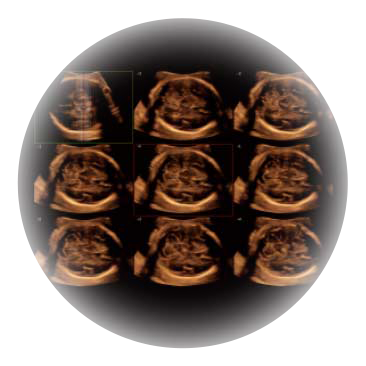

自动获取标准切面,自动完成测量,帮助医生快速完成检查,同时提升测量准确性。